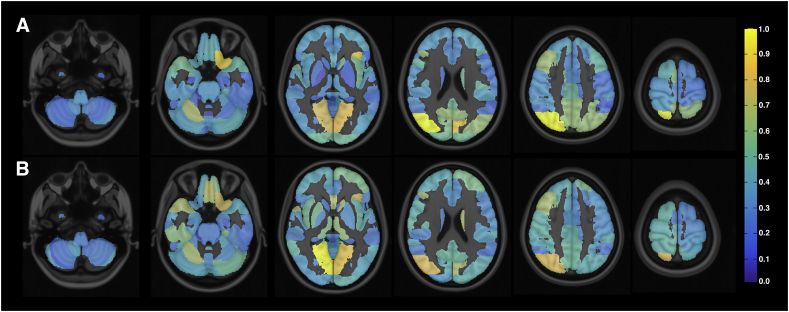

Fig. 2 presents the normalized sum of weights of different brain areas for the two analyzed cases considering the DTI connectivity and rsfMRI correlation features, thus representing the importance of each area for the classification. The most important areas when comparing all the RRMS patients with healthy subjects were (in descending order) the right superior division of the occipital cortex, left frontal orbital cortex, left cuneal cortex, and bilateral lingual gyrus. The most important areas when comparing only the RRMS patients with EDSS >1.5 with healthy subjects were practically the same, but in a different order: the bilateral lingual gyrus, right superior division of the occipital cortex, left frontal orbital cortex, and medial frontal cortex.

Fig. 2.

Discriminating brain regions according to absolute values of feature weights of resulting SVM models. A) Relative weights of SVM classifier between all RRMS patients vs. healthy subjects. B) Relative weights of SVM classifier between RRMS patients with EDSS >1.5 vs. healthy subjects. The results were computed by adding all the weights associated with each area and then normalizing the values. The most discriminating areas are associated with higher weight values.